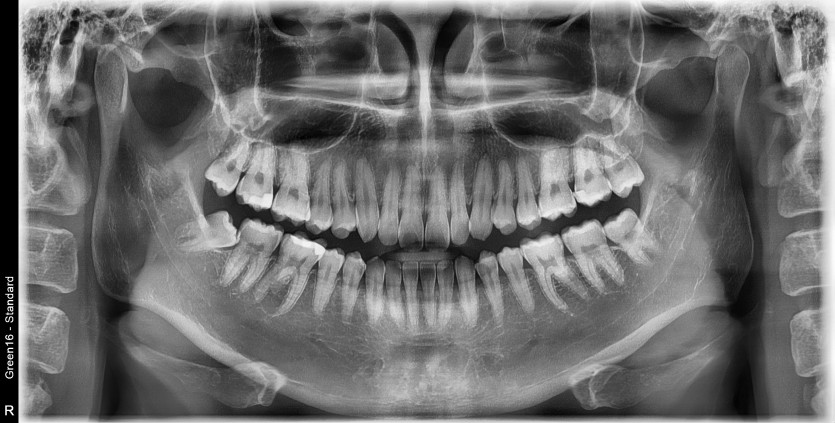

#48 사랑니 발치

구강 외과 전문의가 당일 발치했습니다.